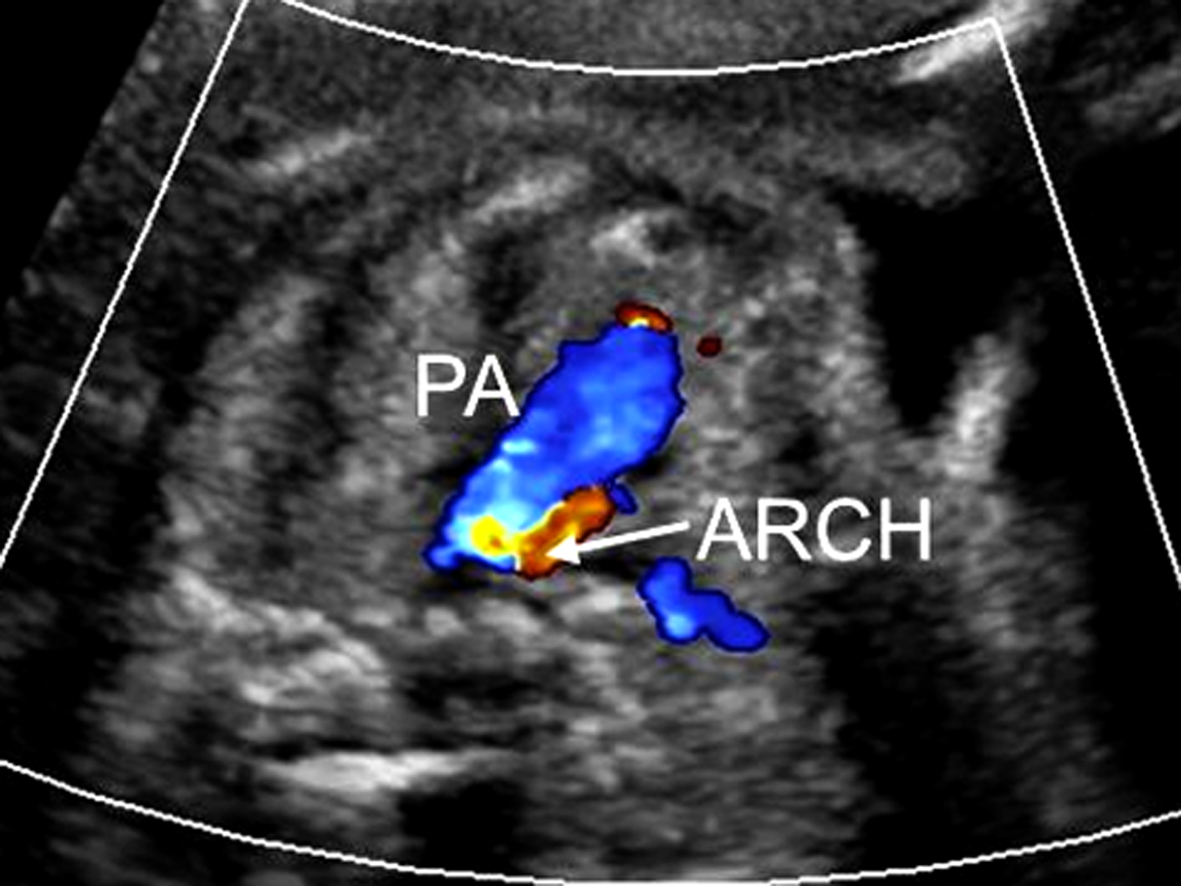

2. 超声诊断要点 二维超声显示左、右心室不对称,左心室明显小于右心室,心轴明显左偏;如伴有二尖瓣闭锁,则左心室内可不显示彩色多普勒血流信号(图1)。彩色多普勒超声检查三血管气管切面主动脉弓与动脉导管血流方向不一致,主动脉弓血流不是流向降主动脉,而是由动脉导管反流而来(图2)。

图2 胎儿左心发育不良综合征:三血管气管切面呈逆向血流信号